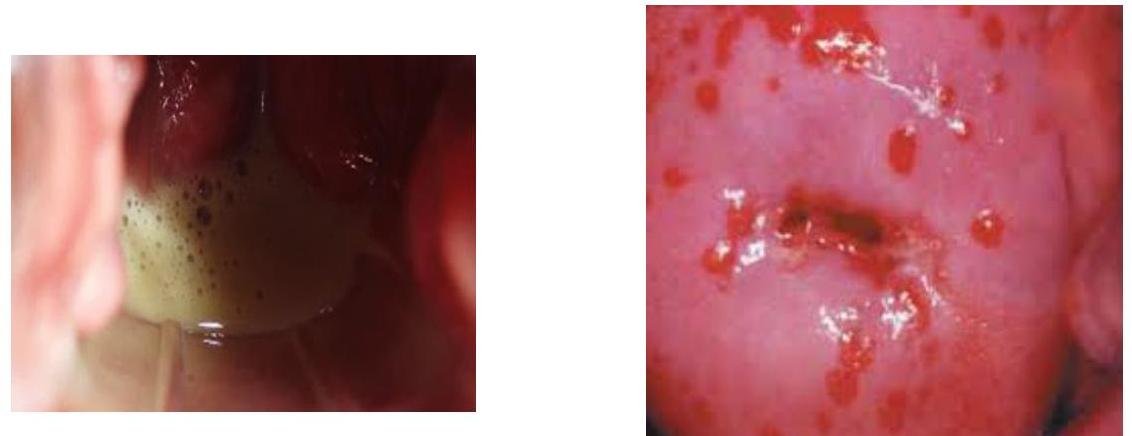

# VAGINITIS INFECCIOSA ## DEFINICIÓN La Cervicovaginitis infecciosa es la inflamación de la mucosa vaginal, cuya causa generalmente se debe a infecciones por hongos (cándida), bacterias (Vaginosis) y el protozoario Tricomonas Vaginalis (Tricomoniasis). Se caracteriza por uno o más de los siguientes signos y síntomas: aumento en la cantidad de la secreción vaginal (flujo), prurito, ardor, irritación, disuria, dispareunia y fetidez o mal olor vaginal; secundario a la presencia de microorganismos patógenos, ## SECRECIÓN NORMAL - Inodoro - Clara - Viscosa - pH ácido 4.5 o menos - Ausencia de nuetrófilos - Responde a cambios hormonales del ciclo menstrual. ## FIORA VAGINAL NORMAL - Lactobacilos - Garnerella Vaginalis - Escherichia Coli - Estreptococo B. - Micoplasmo Hominis - Cándida Albicans ## EPIDEMIOLOGÍA - Representa una de las primeras causas de consulta en unidades médicas. - La enfermedad genital aumenta el riesgo de Enfermedad Pélvica Inflamatoria (EPI). - Riesgo aumentado de complicación de embarazo, VIH y problemas de fertilidad. ## FACTORES QUE MODIFICAN LA FLORA VAGINAL - ANTIBIÓTICOS: suprimen el crecimiento de los organismos comensales (predominio de cepas patógenas) - DUCHAS VAGINALES: alteran el pH y suprimen bacterias endógenas - COITO: la introducción de semen eleva el pH tan alto como 7.2 por 6-8 horas, haciendo susceptible la recepción de patógenos. - CUERPO EXTRAÑO: altera dramáticamente los mecanismos de limpieza vaginal ## ETIOLOGÍA | Vaginosis Bacteriana | 40-50 % | | :-- | :-- | | Candidiasis Vaginal | 20-25 % | | Tricomoniasis | <15 % | | Otros: Chlamydia, N. gonorrhoeae, Mycoplasma | Menor porcentaje | # VAGINOSIS BACTERIANA ## DEFINICIÓN Infección bacteriana producida por la sustitución de la flora vaginal saprofita normal por altas concentraciones de Gardnerella vaginalis, Micplasma hominisy bacterias anaerobias. Es una infección polimicrobiana resultado de remplazo de peróxido de hidrógeno normal que produce el lactobacilo, generando crecimiento excesivo de organismos predominantemente, perdiendo acidez vaginal con un Ph mayor de 4.5, no considerada como infección de transmisión sexual, ya que algunas mujeres sin vida sexual la presentan.  healthy vaginal mucosa  bacterial vaginosis ## EPIDEMIOLOGÍA - Es la infección vaginal más predominante en mujeres en edad reproductiva. - Prevalencia en Latinoamérica 41 - 49 % - Su presencia en el embarazo se relaciona con abortos, partos prematuros, RPM y Endometritis. - Su presencia no hace necesario dar tratamiento o seguimiento a la pareja. ## FACTORES DE RIESGO - Lavado vaginal (duchas vaginales) - Cunnilingus receptivo - Raza negra - Reciente cambio de pareja sexual - Tabaquismo - Uso de anticonceptivos hormonales - Infección de transmisión sexual (ITS) ## CLÍNICA ASINTOMÁTICA: alrededor del 50% de las pacientes son asintomáticas. - LEUCORREA o flujo vaingal fluido, de color blanco o grisáceo. - Fetidez con olor a pescado - No produce dolor, ni comezón, ni irritación. # DIAGNÓSTICO ## GOLD STANDARD: PUNTUACIÓN DE NUGENT - Es un sistema de puntos basado en la suma ponderada de los siguientes morfotipos bacterianos: - Bacilos Gram positivos tipo lactobacillus, Cocobacilos Gram variables pleomórficos tipo ardnerella/bacteroides y Bacilos Gram negativos curvos tipo mobiluncus spp ## CRITERIOS DE AMSEL ## pH Vaginal >4.5 Flujo vaginal grisáceo-blanco, líquido, con olor a pescado Prueba de Aminas con KOH+ (Prueba de Whiff) Presencia de Células Clave en al menos 20% de las células en Fortis (el dato más específico) ## PRUEBA DE AMINAS - Consite en añadir una gota de Hidróxido de Potasio (KOH) al 10% a una muestra de flujo vaginal. - La respuesta positiva se produce mediante la liberación de aminas que conlleva la aparición de un olor fétido. ## pH VAGINAL - En la vaginosis bacteriana el pH asciende por arriba de 4.5 ## FROTIS CON TINCIÓN DE GRAM - Se observan Células Clave (clue-cells) por fijación de cocobacilos en la superficie de las células vaginales.  Células vaginales normales vistas al microscopio. ## CRITERIOS DE HAY/ISON | Grado 1 (Normal) | Predominan los Lactobacilos | | :-- | :-- | | Grado 2 (Intermedio) | Existe flora mixta con algunos lactobacilos presentes, pero también se observan morfotipos de Garnerella o Mobiluncis | | Grado 3 (Vaginosis Bacteriana) | Predominan Gardnerella o Mobiluncus, se observan pocos lactobacilos o asuencia de ellos. | # TRATAMIENTO El tratamiento se inicia cunado sean sintomáticas o asintomáticas que requieran procedimientos quirúrgicos o deseo de ser tratadas. Si la paciente cuenta con DIU, se recomienda cambiar de MPF. ## 1ra elección: METRONIDAZOL - Vía oral 500 mg cada 12 horas por 5-7 días - Vía oral 2.0 g en dosis única - Vía Vaginal local por 5 días ## 2da elección: Tinidazol ## 3ra elección (Alergia a Imidazoles): CLINDAMICINA - Vía oral 300 mg cada 12 horas por 7 días - Vía oral 2 g en dosis única - Vía vaginal 100 mg por 3 días. - Vía vaginal (CREMA) 2% cada 24 horas por 7 días. ## EMBARAZADAS ## 1ra elección: METRONIDAZOL VÍA ORAL - Indicado en sintomáticas con antecedente de parto pretérmino o RPM. ## LACTANCIA ## 1ra elección: METRONIDAZOL 500 mg - No se debe utilizar el esquema de dosis altas ( 2 g ) porque afecta el sabor de la leche materna. - Contraindicada la Clindamicina durante lactancia. # CANDIDIASIS VAGINAL ## DEFINICIÓN También llamada VAGINITIS MONILIÁSICA; es una infección vaginal que est causada por el hongo Cándida albicans en un 80-90 % de los casos, teniendo como síntoma principal el prurito y escozor en la vulva y vagina. La candidiasis se produce por la proliferación de patógenos oportunistas ante cambios en el medio vaginal, en la flora bacteriana local o en la resistencia del huésped. ## EPIDEMIOLOGÍA La cándida es un hongo ssaprofito aislado frecuentemente en el tracto genital inferior, si aumenta su concentración origina una vaginitis sintomática. ## FACTORES DE RIESGO - Diabetes Descontrolada - Uso de anticonceptivos Orales - Obesidad - Uso reciente de Antibióticos ## CLÍNICA - Secreción adherente a la mucosa, blanquecino, con grumos (Queso Cottage) - No es fétida - Pruriginosa - Inflamación vulvovaginal - Fisuras - Eritema o enrojecimiento importante - Molestia al orinar - Uso de corticoesteroides - Quimioterapia - Inmunocomprometidos  [^0] [^0]: NO COMPLICADA - Generalmente producida por cándida albicans - Evento esporádico o poco frecuente - Molestias leves o moderadas - No hay inmunocompromiso COMPLICADA - Asociada a C. glabrata, C. tropicalis y C. krusei. - RECURRENTE: 4 o más episodios por año, síntomas y signos severos - Cuadros en DM o Inmunosupresión y resistencia al tratamiento. # DIAGNÓSTICO ## GOLD STANDARD: CULTIVO - Indicado solamente en casos de recurrencia o Candidias Complicada ## FROTIS EN FRESCO - Se realiza con Solución Salina al 0.9% - Se observan PSEUDOHIFAS, BLASTOSPORAS, LEVADURAS O MICELIOS. ## pH Vaginal - En la Candidiasis Vaginal no suele variar (se mantiene entre 4 - 4 .5) ## TINCIÓN DE GRAM ## ESTUDIO CITOLÓGICO CERVICO-VAGINAL   ## REFERENCIA A 2ㅇ NIVEL: - Portadoras de VIH - Sin respuesta a tratamiento - Mujeres con Candidiasis Vuvlovaginal diferente a C. albicans que no responden a tratamiento. # TRATAMIENTO Todos los azoles tópicos y orales, así como la Nistatina Local, tienen una efectividad alrededor del 80 % en el tratamiento de la candidiasis vulvovaginal no complicada. No es necesario dar tratamiento a la pareja sexual. Los Azoles están CONTRAINDICADOS en Embarazo y Lactancia ## TRATAMIENTO TÓPICO ## 1ra elección: MICONAZOL CREMA 2% - Aplicar 5 gramos en vulva y vagina cada 24 hroas durante 14 días - Efectos secundarios: irritación vaginal 2da elección: NISTATINA ÓVULOS VAGINALES DE 100,000 UI - Una aplicación vaginal cada 24 horas durante 14 días ## TRATAMIENTO ORAL - FLUCONAZOL 150mg dosis única - ITRACONAZOL 200 mg cada 12 horas por 1 día ## EMBARAZO - Las mujeres asintomáticas con candidiasis vaginal no requieren tratamiento. ## CANDIDIASIS RECURRENTE (>4 episodios al año) ## 1ra elección: INDUCCIÓN: a) Ketoconazol 200 mg (media tableta) cada 24 horas por 14 días b) Miconazol Crema 2%, 1 aplicación intravaginal diaria por 14 días ## MANTENIMEINTO a) Ketoconazol 200 mg (media tableta) diaria durante 6 meses. b) Itraconazol 50 - 100 mg diarios durante 6 meses. c) Fluconazol 100 mg una vez a la semana durante 6 meses. (c) Copyright 2021-2022 Joyas ENARM - Todos los derechos reservados - # TRLGOMONIASTS ## DEFINICIÓN Se tratada de una infección de TRANSMISIÓN SEXUAL de origen no viral, con una elevada prevalencia. Es producida por un PROTOZOO ANAEROBIO, TRICHOMONA VAGINALIS y se puede asociar a o otros microorganismos como el gonococo y chlamydia. ## EPIDEMIOLOGÍA - Se debe promover el uso de preservativo en las relaciones sexuales. - En casos recurrentes se sospechará en VIH. - Evitar las relaciones sexuales incluyendo el sexo oral hasta que el binómio se haya recuperado. ## FACTORES DE RIESGO - Múltiples parejas sexuales - Relaciones sexuales sin uso de preservativo. ## CLÍNICA - Flujo anormal, con leucorrea amarillentea abudante, espumosa y gaseosa - Cérvix en fresa o con puntilleo rosado - Fetidez vaginal - Disuria (cuando hay infección uretral) - Dolor pélvico bajo - Vulvitis, vaginitis (edema, eritema, cervicitis) EN EL 90% DE LOS CASOS TAMBIÉN HAY INFECCIÓN EN LA URETRA Y GLÁNDULAS PARA-URETERALES.  (c) Copyright 2021-2022 Joyas ENARM - Todos los derechos reservados - # DIAGNÓSTICO ## iiGOLD STANDARD: CULTIVO VAGINAL!! - Se utiliza el Medio de Cultivo DIAMOND FORTIS CONVENCIONAL DE PAPANICOLAU - El reporte de Tricomonas en la citología cervical solo tiene \mathbf{5 8 %} sensibilidad y 8% de falsos positivos. ## MICROSCOPÍA - Tiene una sensibilità del 60% - Se visualiza el protozoo que tiene FORMA DE PERA CON CILIOS EN UN EXTREMO y puede verse su movilidad. PRUEBAS DE ÁCIDO NUCLÉTICO (NAT) ## PUNTO DE ATENCIÓN DE PRUEBAS - Puede ser la prueba rápida de antígenos o sonda de ADN. ## TRATAMIENTO La mayoría de las cepas de Trichomona son muy sensibles al Metronidazol y fármacos relacionados, teniendo una tasa de curación del 95 %. El tratamiento debe darse a ambos miembros de la pareja para erradicar la ETS, evitar relaciones sexuales e ingesta de alcohol (efecto Antabuse) ## 1ra elección: METRONIDAZOL SISTEMICO - Vía oral 500 mg cada 12 horas por 7 días - Vía oral 2 g en dosis única (puede utilizarse en el embarazo) 2da elección: TINIDAZOL SISTÉMICO - Vía oral 2 g en dosis única ## LACTANCIA - Se deberá suspender la lactancia en caso de requerir el uso de Metronidazol. - Suspenderla por lo menos 12 - 24 horas y reiniciar al concluir el medicamento. ## FALLA EN EL TRATAMIENTO Se deberá valorar: a. Cumplimiento del tratamiento y excluir que haya vomitado el Metronidazol b. Posibilidad de reinfección c. Que la pareja no haya recibido tratamiento (c) Copyright 2021-2022 Joyas ENARM - Todos los derechos reservados - # CLAMIDIA ## DEFINICIÓN La infección por Chlamydia trachomatis es una enfermedad de transmisión sexual cuyo agente causal es la Chlamydia trachomatis que tiene afinidad por mucosa (uretra, endocérvix, recto, faringe y conjuntiva). Clínicamente puede presentarse como: cervicitis, cistitis, uretritis, cervicovaginitis, salpingitis, enfermedad pélvica inflamatoria EPI y Síndrome de Fitz- Hugh -Curtis. En la mujer, se asocia con complicaciones a largo plazo como obstrucción tubaria, embarazo ectópico e infertilidad; en el caso de los varones, condiciona orquitis y epididimitis. ## EPIDEMIOLOGÍA - Alta prevalencia de complicaciones como Embarazo Ectópico, EPI, Infertilidad - Puede ser asintomática, detectándose a través de tamizajes o revisión ginecológica incidental. ## FACTORES DE RIESGO - Mujeres menores de 25 años de edad con actividad sexual - Mujeres mayores de 25 años de edad con dos o más parejas en el último año. - Pacientes que asisten por alguna infección de transmisión sexual. - Parejas sexuales de individuos positivos a Chlamydia trachomatis. - Parejas sexuales de aquellos con condiciones para presentar infección por Chlamydia trachomatis, como padecer una EPI o epidídimo-orquitis. - Madres de lactantes con conjuntivitis o neumonitis por Chlamydia trachomatis. ## CLÍNICA - Dolor al orinar - Secreción Uretral - Dolor en hipogastrio - Prurito y escozor vaginal durante el coito - Leucorrea amrillenta y fetidez - pH mayor a 4.5 # DIAGNÓSTICO GOLD STANDARD: PCR ## TAMIZAJE - Con muestras de orina que detectan Chlamydia. AMPLICACIÓN DE ÁCIDOS NUCLEICOS (NATS) RADIOINMUNOANÁLISIS CULTIVO ## TRATAMIENTO ## 1ra elección: a) AZITROMICINA 1 g oral dosis única b) DOXICILINA 100 mg oral cada 12 horas por 7 días (contraindicada en embarazo) ## 2da elección: a) Eritromicina 500 mg oral cada 6 horas por 7 días b) Levofloxacino 500 mg oral cada 24 horas por 7 días (contraindicada en embarazo) c) Ofloxacino 300 mg cada 12 horas por 7 días Si no se puede administrar Azitromicina o Eritrmoicina -\rightarrow Amoxicilina o Clindamicina pueden ser consideradas.